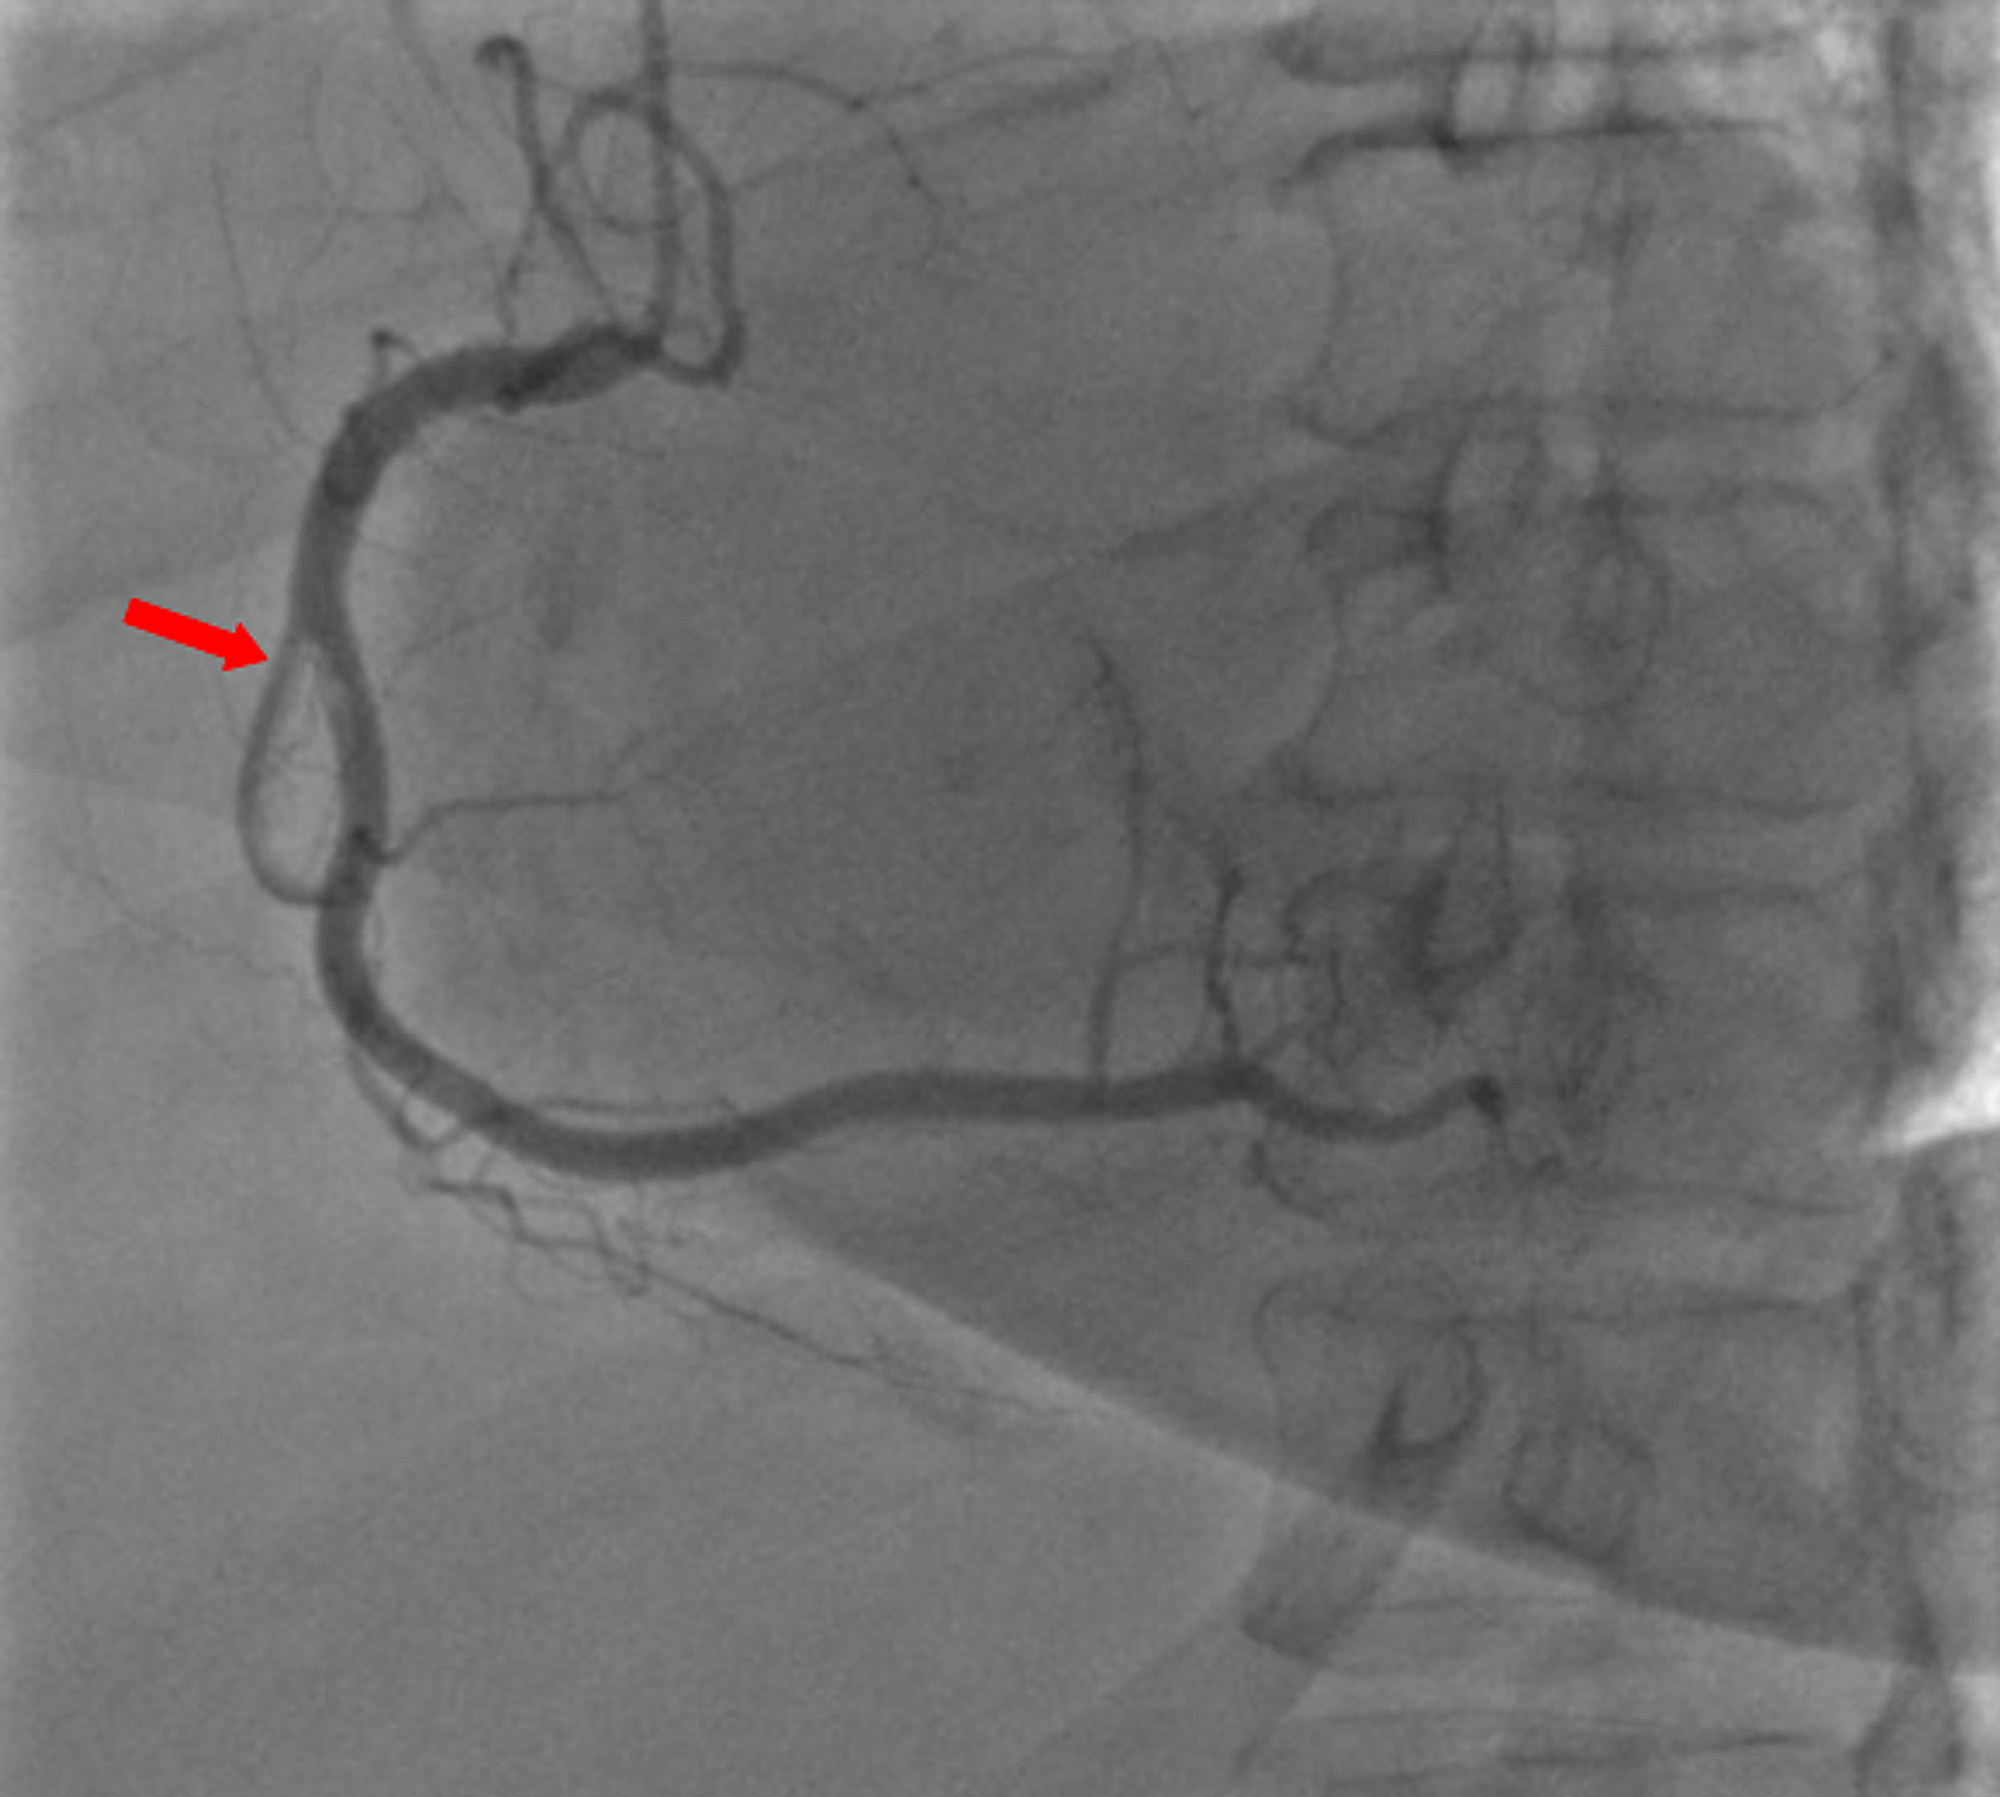

A 59-year-old woman was admitted to the emergency department with sudden onset of chest pain for five hours. She had hypertension (treated with β-blockers) as a cardiovascular risk factor. She was diagnosed with advanced non-small-cell lung cancer with liver metastases one month previously. The patient was not considered for surgical resection, she was scheduled for chemotherapy, and, consequently, no antineoplastic treatment had been initiated yet. Prophylactic anticoagulation was not indicated On clinical examination, her blood pressure was 150/90 mmHg with a pulse of 100 beats per minute, oxygen saturation of 95%, and normal heart sounds. The 12-lead electrocardiogram showed sinus rhythm with a heart rate of 102 beats for minutes and ST-segment elevation in all leads except aVR where ST-segment depression was noted (Figure 1). Her laboratory test results revealed a baseline troponin T level of 1212 ng/ml (normal range < 26 ng/ml). Also, the echocardiography findings revealed akinetic walls from the mid to apical septum and anterior and inferior walls. The ejection fraction was estimated to be 39%. Therapy was started with clopidogrel, aspirin, and low-molecular-weight heparin. The patient underwent a coronary angiogram from the right radial approach, which revealed the presence of an extended thrombus in the left anterior descending artery (LAD), and another thrombus was found in the second segment of the right coronary artery (RCA) with thrombolysis in myocardial ischemia (TIMI) III flow and without any atherosclerotic lesions in the coronary artery tree (Figure 2 and Figure 3), therefore, balloon angioplasty and/or stent placement was not considered. The patient was taken to the coronary care unit (CCU) and tirofiban infusion was administered for a period of 48 hours. In view of persistent breathlessness, pulmonary embolism was suspected. There were no symptoms or clinical signs suggestive of deep venous thrombosis. A computed tomographic pulmonary angiography was performed and showed a distal pulmonary embolism (Figure 4). The patient was discharged on acenocoumarol to be followed as an outpatient. At her 45 days follow-up, she did not report any episode of chest pain, bleeding, as well as any thrombotic events.